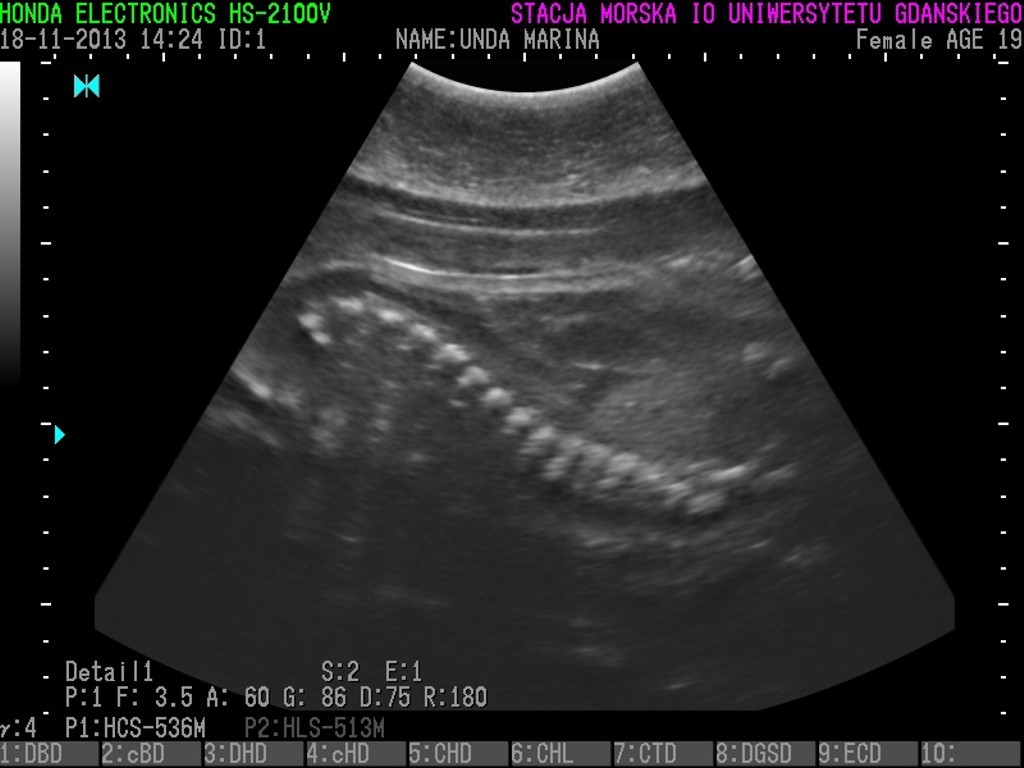

Unda Marina, Ewa i Ania urodzą? Badania 3 fok wskazały, że znajdują się w zaawansowanej ciąży i jeśli nie wydarzą się żadne nieprzewidziane okoliczności, na początku marca możemy spodziewać się trzech młodych osobników.

Dzięki specjalistycznemu sprzętowi, zakupionemu przy wsparciu WWF wiadomo, że focza ciąża przebiega obecnie bez większych problemów. Wkrótce będziemy mogli poznać również płeć fok.